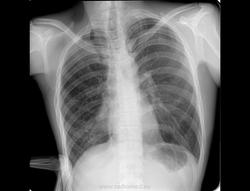

Молодой человек 1977 г.р, прошел профосмотр. Что-то смущает?

Ничего не смущает. Нужна томография верхушек.

Валентин Львович, здравствуйте. Вот и я пропустила патологию, а вернулась к этому пациенту через 8 месяцев, когда он заболел туберкулезом легких

Я бы тоже за верхушки не зацепилась, а правое легочное поле в нижнем отделе сразу напрягло.Мне показалось, что какой-то клубок  сосудов(?).

Странно смотрится все правое легочное поле, может гипоплазия с аномалией сосудов корня?

Аномалия легочной вены правого легкого (ЧАДЛВ). Ятаган синдром. Показано МСКТ с внутривенным болюсным контрастированием.

Затемнение паравертебрально справа в нижнем отделе, на фоне которого визуализируются просветы бронхов - ателектаз? Верхняя доля компенсаторно вздута.

Всем, здравствуйте. Результатов МСКТ -снимков не дождалась; мать не принесла. Есть только протокол. Докладываю: пациент яв-ся инвалидом детства по- психическому заболеванию,  правосторонний гемипарез с рождения, в анамнезе частые простудные заболевания, правосторонние н/долевые пневмонии, туберкулез легких - ЧДБ.

Заключение: Гипоплазия н/доли правого легкого. Компенсаторная эмфизема левого легкого.

Да, впервые. Со слов матери была проведена и ФБС. Я пришла к выводу, что имея одну вр.патологию, надо всегда предполагать о наличии и других, как в данном случае; хотя данного мальчика я знаю с детства и сама лечила неоднократно пр.пневмонию, будучи терапевтом.